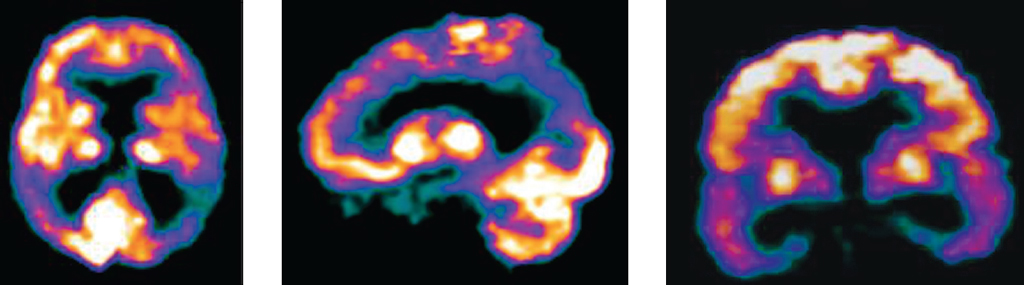

In mild Alzheimer-type dementia, the most severe decrease in metabolism is observed in the hippocampal plane. The progression of cognitive deficiency was associated with a further decrease in parietotemporal cortex metabolism, which was symmetrical and relatively selective compared to other examined areas (Figure 1).

Fig. 1. Alzheimer’s disease, mild dementia: impaired accumulation of 18F-FDG in the projection of the parietal, temporal lobes, hippocampus, posterior cingulate gyrus

Рис. 1. БА, легкая деменция: нарушение накопления 18F-ФДГ в проекции теменных, височных долей, гиппокампов, заднего отдела поясной извилины